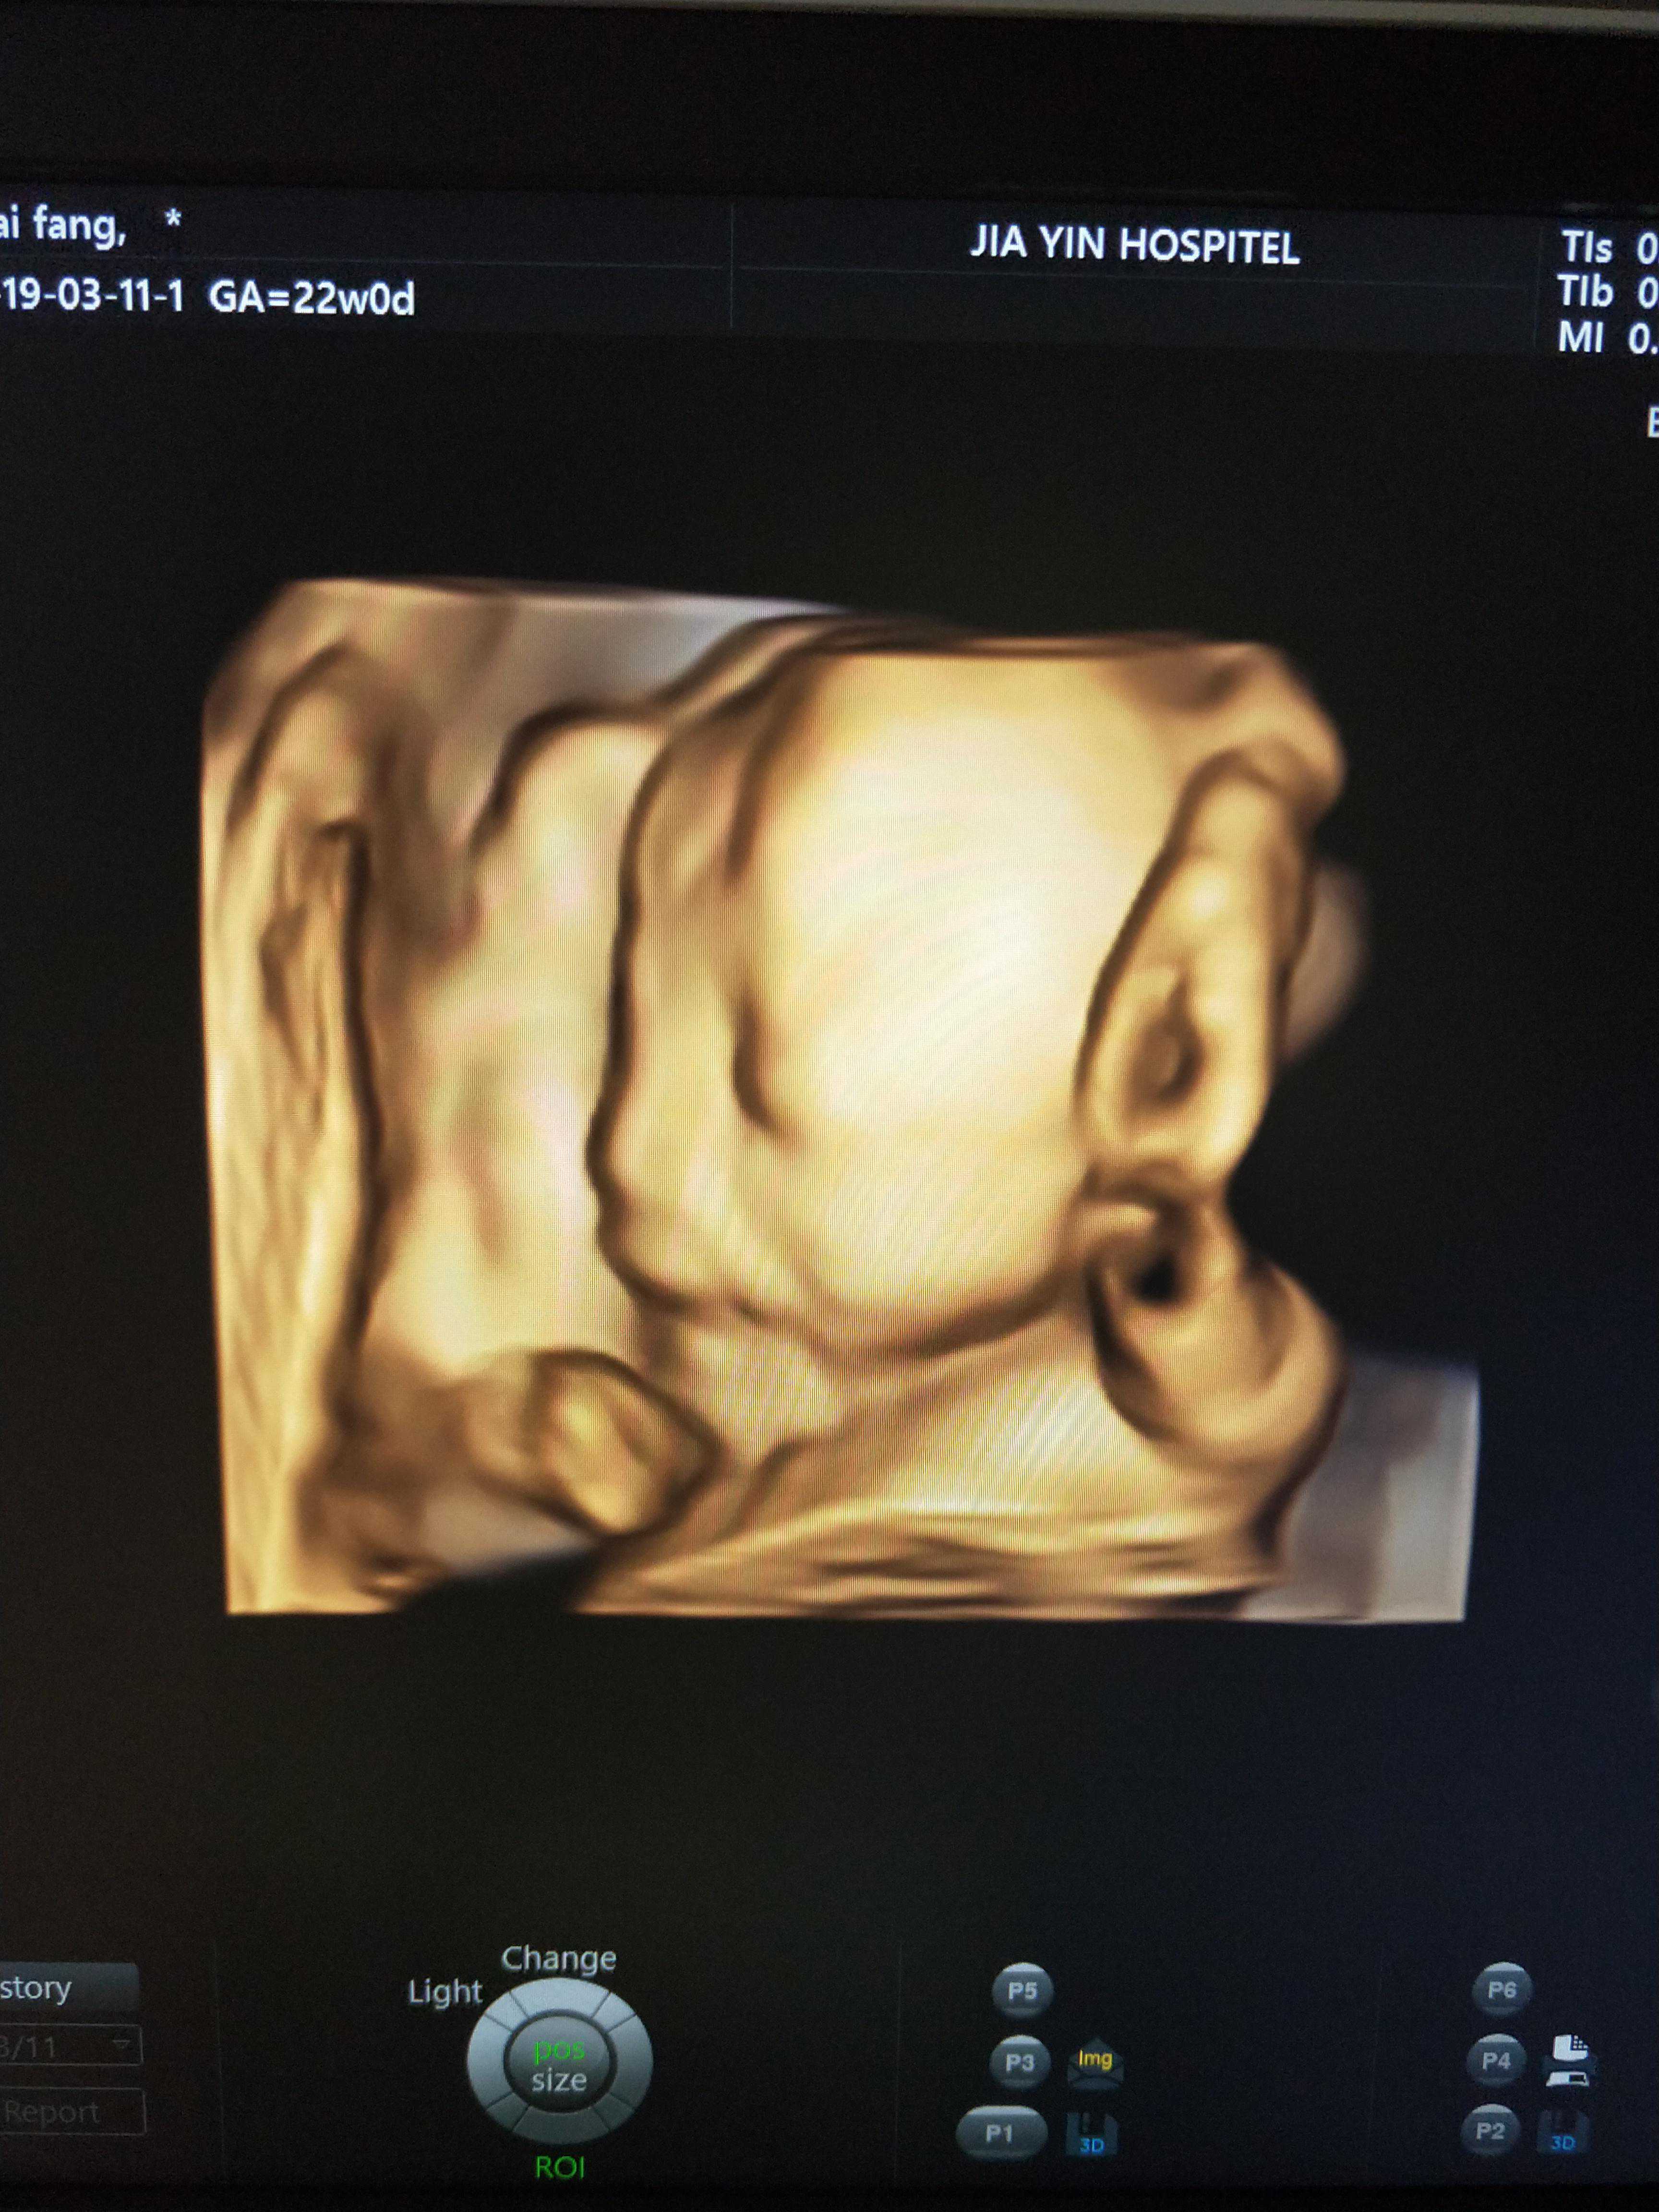

熬到20周做四维的时候正好我老公又出差,每次他在关键时刻掉链子,那天我和二姐早早就去了,人不多,但也遇到问题了,一个胎儿看了两遍就全看清楚了没有问题,另外一个不活动,后背的地方看不到,于是医生就让我先走走,走完过了一个小时左右测的还不行,然后让我跪在床上十五分钟再试试,还不行,折腾了一上午也没把另外一个胎儿看清楚,没办法下午继续。

下午第一个做的就是我,进去以后一看又不行,接着趴,在等候区的沙发上又趴了十几分钟,我二姐说她生她家老大的时候胎位不正,也是这么趴,都趴了一个多星期,哎,女人真心累!趴完以后又进去还是不行,医生没让我出去直接在做B超的床上让我趴了十分钟左右,她说反正下午也没人就你一个也别出去趴了,就在这儿吧!最后终于趴成功了,也是够累的,医生说我这两个一天做完已经很好了,有的都做两天呢!好吧,我还挺幸运的。